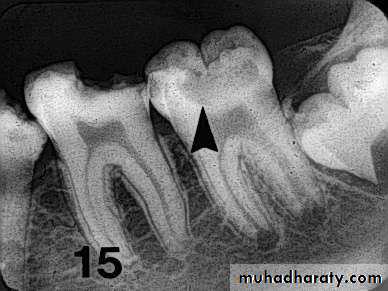

Carious lesions are detectable radio graphically when there has been enough demineralization to allow it to be differentiate from normal.They are valuable in detecting proximal caries which may go undetected during clinical examination.

On average they have around 50% to 70% sensitivity in detecting carious lesions.

40% demineralization is required for definitive decision on caries

Incipient occlusal lesions

Moderate occlusal lesionsSevere occlusal lesions

Advanced proximal lesions

Incipient proximal lesionsModerate proximal lesions

OTHER RADIOGRAPHIC SHADOWS

Radiolucent Cervical Burn out:- Evident at the neck of tooth

well demarcated above by

enamel cap& below by alveolar

bone level

- It is triangular in shape

being less apparent at the center

of tooth

-good alveolar bone height

will enhance cervical burn-out

Radiopaque zone beneath amalgam restorations

dentinTin & zinc ions are released into underlying